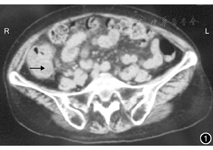

患者女,71岁。因右髂区疼痛反复发作8个月余,加重1周于2013年3月12日入院。8个月前无明显诱因出现右髂区疼痛,疼痛持续不缓解,恶心无呕吐,发热(体温未测),无寒战,无腹胀及腹泻。曾在外院就诊,诊断为阑尾周围脓肿。保守治疗缓解后出院。此后又反复发作3次,就诊于当地多家医院,均诊断为阑尾周围脓肿,保守治疗好转。此次入院前1个月在外院行胃镜及肠镜检查未发现异常。1周前无明显诱因再次出现上述症状,为求进一步诊断与治疗,收入我院。患者精神欠佳,食欲差,大、小便无明显异常,体质量无明显下降。既往有甲状腺功能亢进、颈椎病病史。入院体格检查:体温正常。急性病容,表情痛苦,全身皮肤及巩膜无黄染。腹部轻度膨隆,无胃肠型及蠕动波,右髂区饱满,未触及明确包块,局部压痛、反跳痛及轻度肌紧张,叩诊无异常,肠鸣音正常。B超检查:(1)阑尾区见一低回声以实性为主的混合性包块,大小为9.9 cm×4.8 cm×4.9 cm,轮廓尚清晰,回声不均,内见点状血流。(2)与之相连的回盲部肠壁不规则增厚,最大厚度为1.7 cm,回声减低。(3)包块周围见多个肿大淋巴结,回声减低,轮廓清晰。B超检查诊断为右髂区新生物,多考虑阑尾肿瘤(恶性),回盲部淋巴结肿大。CT检查:右髂区局部肠管壁增厚,管腔扩张,管壁周围密度欠均匀(图1)。CT检查诊断为阑尾占位性病变可能性大。肿瘤学指标:AFP正常,CEA为14.04 μg/L,CA50>300 kU/L,CA19-9>200 kU/L。因患者1个月前在外院已行肠镜检查,拒绝再次行肠镜检查。因包块与肠管包裹,超声引导下穿刺活组织检查操作可能导致副损伤,而放弃此项检查。